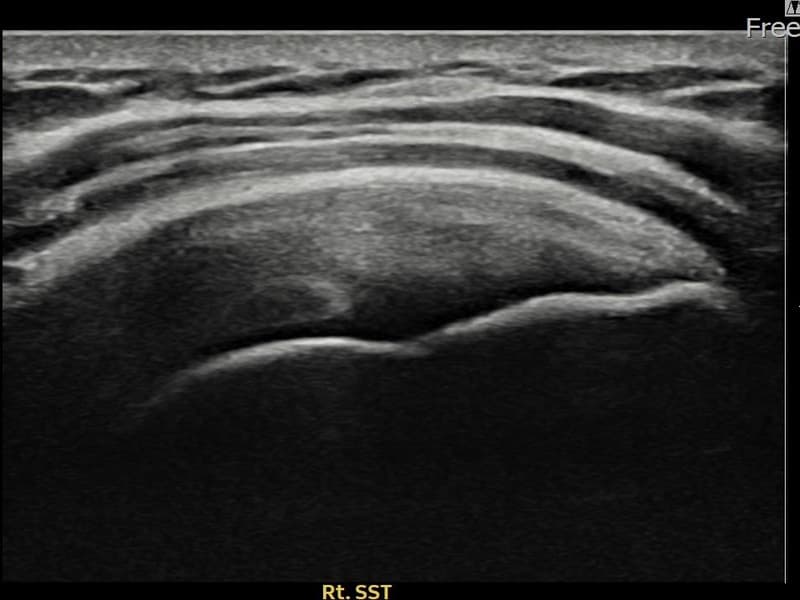

시술 전 초음파 측정 결과 파열 크기는 8mm × 3mm (힘줄 두께의 약 32% 결손)로 확인되었습니다. 시술 전 초음파에서 우측 견갑하근건 내 에코 단절과 힘줄 결손 소견이 확인되었습니다. 시술 후 초음파에서 결손 부위에 재생 조직이 채워지고 힘줄 연속성이 회복된 것이 관찰되었습니다.

30대 후반 남성 환자분으로, 우측 어깨 전방 통증이 수개월째 지속되어 내원하셨습니다. 팔을 앞으로 들어 올리거나 머리 위로 뻗는 동작 시 통증이 심하고, 무거운 것을 들거나 밀 때 어깨 앞쪽에 힘이 빠지는 느낌이 있다고 하셨습니다. 초음파 검사에서 우측 견갑하근건 부분파열이 확인되었으며, 초음파 유도 하 축소봉합술을 시행하였습니다. 시술 후 보조기 착용과 단계적 재활 운동을 진행하였고, 시술 후 추적 초음파에서 힘줄 연속성이 회복되어 어깨 기능이 정상화되었습니다.